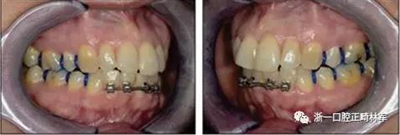

由于下頜中切牙間沒(méi)有間隙行下頜正中切開(kāi)術(shù),故進(jìn)行術(shù)前正畸擴(kuò)展間隙。下頜前牙粘托槽,中切牙托槽成交放置,將中切牙牙根分開(kāi)。使用0.018X0.018鎳鈦絲及置于下頜左、右中切牙之間的推簧推間隙。3個(gè)月后拍攝CBCT示已有足夠間隙行下頜正中截骨術(shù)。

手術(shù)前三周,上、下頜磨牙和前磨牙使用分壓圈進(jìn)行分牙。術(shù)前一天,去除下頜切牙托槽,安裝hyrax擴(kuò)弓器。

全麻下進(jìn)行上頜骨腭中縫骨皮質(zhì)劈開(kāi)及下頜正中劈開(kāi)術(shù)。手術(shù)后,用X光片檢查上頜骨和下頜骨中線切口的位置和方向。

術(shù)后第9天開(kāi)始旋轉(zhuǎn)擴(kuò)弓器,每天轉(zhuǎn)2次,每次轉(zhuǎn)90度,即擴(kuò)開(kāi)0.5mm。每隔1周進(jìn)行檢查,目標(biāo)上頜擴(kuò)開(kāi)9mm,下頜擴(kuò)開(kāi)6mm。18天后,上頜中切牙間出現(xiàn)8mm間隙。下頜出現(xiàn)6mm間隙,(于13天出現(xiàn)后,停止旋轉(zhuǎn)擴(kuò)弓器)。在擴(kuò)弓器旋轉(zhuǎn)3天后,拍片發(fā)現(xiàn)左下頜中切牙遠(yuǎn)中牙根中段有一條低密度陰影,臨床冷熱診反應(yīng)遲鈍,可能為術(shù)中損傷所致。牙體牙髓科會(huì)診,建議行根管治療,故行根管治療。

擴(kuò)弓保持8周后,除擴(kuò)弓器影響牙外粘接托槽,使用0.014鎳鈦絲進(jìn)行排齊、整平。旋轉(zhuǎn)停止后3個(gè)月拆除擴(kuò)弓器,全口粘接托槽,使用0.016niti繼續(xù)排齊整平。佩戴可摘保持器,保持上頜寬度。在使用至0.018x0.018niti7周,徹底排齊整平后,使用大弓型的0.016x0.022不銹鋼絲,繼續(xù)維持原有寬度,同時(shí)停止使用可摘保持器。掛II類(lèi)牽,糾正磨牙關(guān)系,使用鏈圈關(guān)閉散在間隙,少量使用IPR去除局部前牙的黑三角。術(shù)后9個(gè)月拍全景示,牙根平行度可,再無(wú)其他牙根出現(xiàn)問(wèn)題。1年7個(gè)月后治療結(jié)束。上下頜3-3舌側(cè)保持器+哈雷氏保持器進(jìn)行保持。